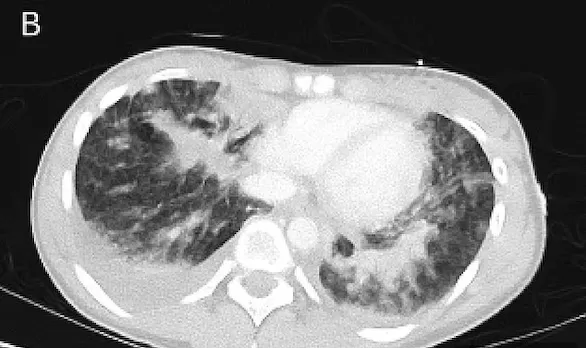

تم تشخيص داكوتا بنقص الأكسجة في غضون ساعات، مما يعني أن رئتيها لم تحصل على ما يكفي من الهواء، وقضت ثلاثة أيام تحت جهاز التنفس.

ويعتقد أطبائها في مستشفى راندويك للأطفال، أنها كانت تعاني من حالة رئوية تسمى “إيفالي” والتي ظهرت لأول مرة في الولايات المتحدة في عام 2019.

يُعتقد أن حالة “إيفالي” وهي اختصار باللغة الإنكليزية يشير إلى إصابات الرئة المرتبطة بالتدخين الإلكتروني، ناتجة عن تدخين سجائر إلكترونية تحتوي على رباعي هيدروكانابينول (THC)، وهي مادة ذات تأثير نفسي توجد أيضًا في الماريجوانا، ومضافات فيتامين E أسيتات.

وقالت ستيفنسون، إن ابنتها كانت مريضة جداً، وأن الأطباء استخرجوا من رئتيها حوالي 10 حقن مليئة بالسوائل المتراكمة في رئيتيها جراء التدخين الإلكتروني.

وبعد أن خرجت داكوتا من المستشفى بعد أسبوع من تلقي العلاج، كانت هناك أورام غير طبيعية تسمى العقيدات لا تزال تظهر في فحوصات الرئة، مما شكل تهديداً خطيراً على حياتها.